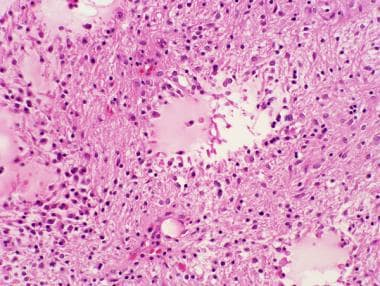

组织学上,毛细胞型星形细胞瘤由细长的双较星形细胞组成,细胞核呈圆形至椭圆形,较常见的是单调型。这些细胞较常见于大脑,在大脑中,坚固的肿瘤细胞排列成不规则的束,与紧密包裹的肿瘤中的嗜酸性颗粒体和罗森塔尔纤维相关,如下图所示。

罗森塔尔纤维是在毛细胞星形细胞瘤过程中发现的细长的嗜酸性蛋白质内含物。化学上,这些纤维由胶质纤维酸性蛋白和α-β晶体蛋白组成。(苏木精、曙红;20倍原始放大倍数。)

如下图所示,这种模式通常被由纺锤体细胞包围的微囊中断,纺锤体细胞随意地向囊肿方向定向,松散的原纤维尾部延伸到充满水的微囊中。

毛细胞星形细胞瘤通常表现为紧密致密细胞被疏松区域和微囊中断的双相外观。(苏木精和曙红,10倍原始放大。)

毛细胞星形细胞瘤疏松区放大倍数更高。(苏木精和曙红,20倍原始放大倍数。)